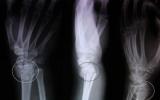

Հիվանդ Ա.Ն., ծնվ.1982թ., 2015թ. ամռան կեսերին`ՀՀ ԶՈՒ սահմանամերձ գոտում ծառայողական պարտականությունները կատարելիս, թշնամու դիպուկահարի կողմից ստացել է հրազենային վիրավորում: Հիվանդը սկզբում տեղափոխվել է Սիսիանի...